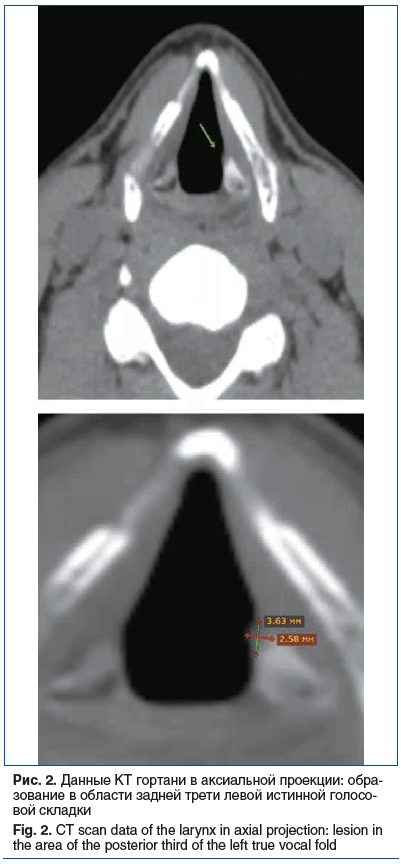

Данные компьютерной томографии (КТ) гортани (рис. 2): в проекции дорсальной трети левой истинной голосовой складки определяется образование размером 3,6×2,5×3,7 мм, контур четкий, выбухает в просвет складочного пространства в среднем до 0,8 мм; уплотнение плотно прилежит к голосовому отростку левого черпаловидного хряща, с локальной эрозией его контура глубиной до 0,9 мм, по периферии левый черпаловидный хрящ в данной области с остеосклерозом плотностью +215 HU (для сравнения: на контралатеральной стороне черпаловидный хрящ в данной области плотностью +73 HU и без остеосклероза).